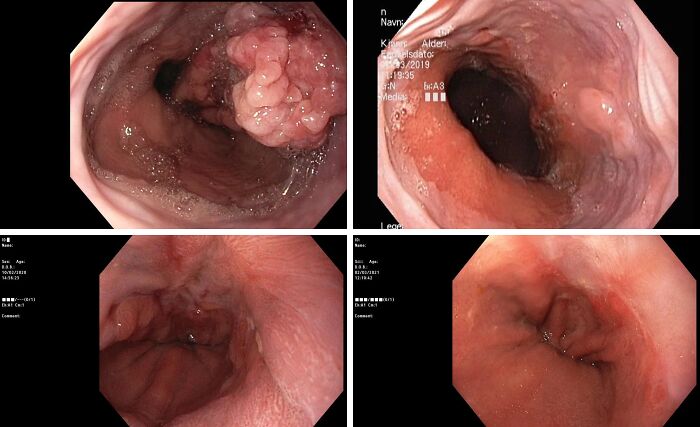

Ever Wondered What A (Esophagus) Tumor Looks Like? 7 Rounds Of Chemo, And This Is The Progress